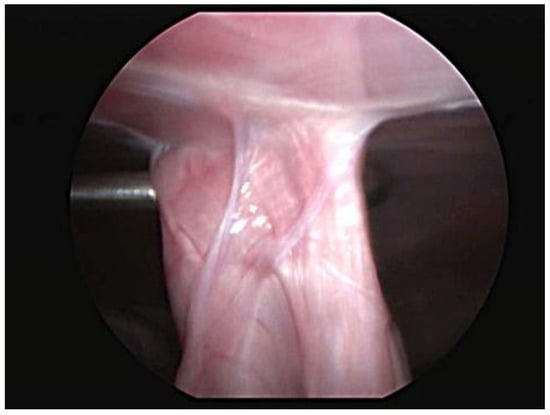

Abdominal ultrasound examinations were available for 29 cases. The last evaluation, which was performed at a median of 6 months (range 3–12 months), showed an intact adhesion at the gastropexy site in all dogs. Four dogs were examined twice, at 3 and 6 months after the total laparoscopic gastropexy, and no significant differences were noted. One dog underwent a CT scan for a complex femur fracture at 8 months postoperatively, and both the endoclip and pexy site were identified. One case had a laparoscopic vasectomy 6 months after surgery, at which time the gastropexy was proven to be intact, and adequate adhesion formation between the body wall and pyloric antrum was observed (Figure 3).

Figure 3.

Laparoscopic view of the intact gastropexy 6 months postoperatively.

Ultrasound evaluation showed an intact gastropexy in all dogs examined. The pyloric antrum of the stomach was observed to be in contact with the right abdominal wall, and no slide sign of the viscera was noted at the site of the pexy. The titanium endoclip was also visible, and it was surrounded by a thin avascular capsule. The examined reports were very similar to those previously described [2,3,5,12,22,23,24,32]. Ultrasound is a noninvasive, repeatable method, and it usually does not require sedation of the animal. However, it cannot be used to establish the quality or strength of a gastropexy. A postoperative laparoscopic evaluation is more useful for assessing the strength of the adhesion [16]. However, due to the invasiveness of the procedure, it was not included in the postoperative follow-up examinations unless another laparoscopic procedure had to be performed. In one case, it was possible to observe the gastropexy site during laparoscopic vasectomy. For this, the stomach was pulled away from the body wall with Babcock forceps to subjectively verify the strength of the adherence, and it was evaluated as being adequate. Computed tomography (CT) can also be considered a valid method to assess the position of the stomach following a gastropexy procedure, but it is much more invasive and expensive [33].